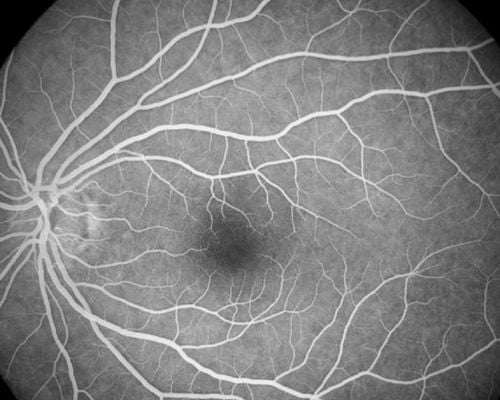

FFA (Fundus Fluorescein Angiogram)

This test is done to see if there is proper blood flow in the blood vessels in the two layers in the back of your eye (the retina and choroid). It can also be used to diagnose problems in the eye or to determine how well certain eye treatments are working. https://medlineplus.gov/ency/article/003846.htm